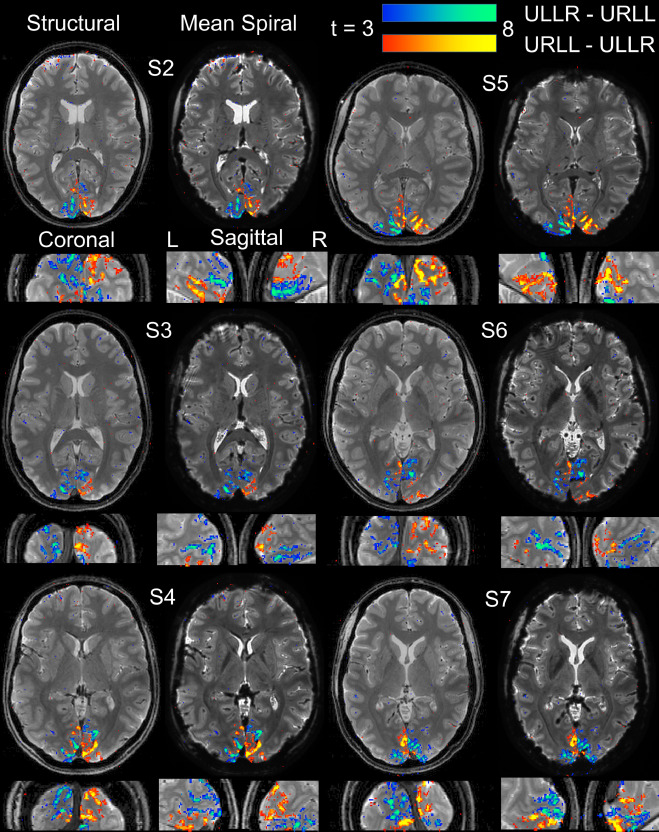

Figure 7: Mean spiral images and activation maps over subjects (S2-S7) for high-resolution spiral-out fMRI.